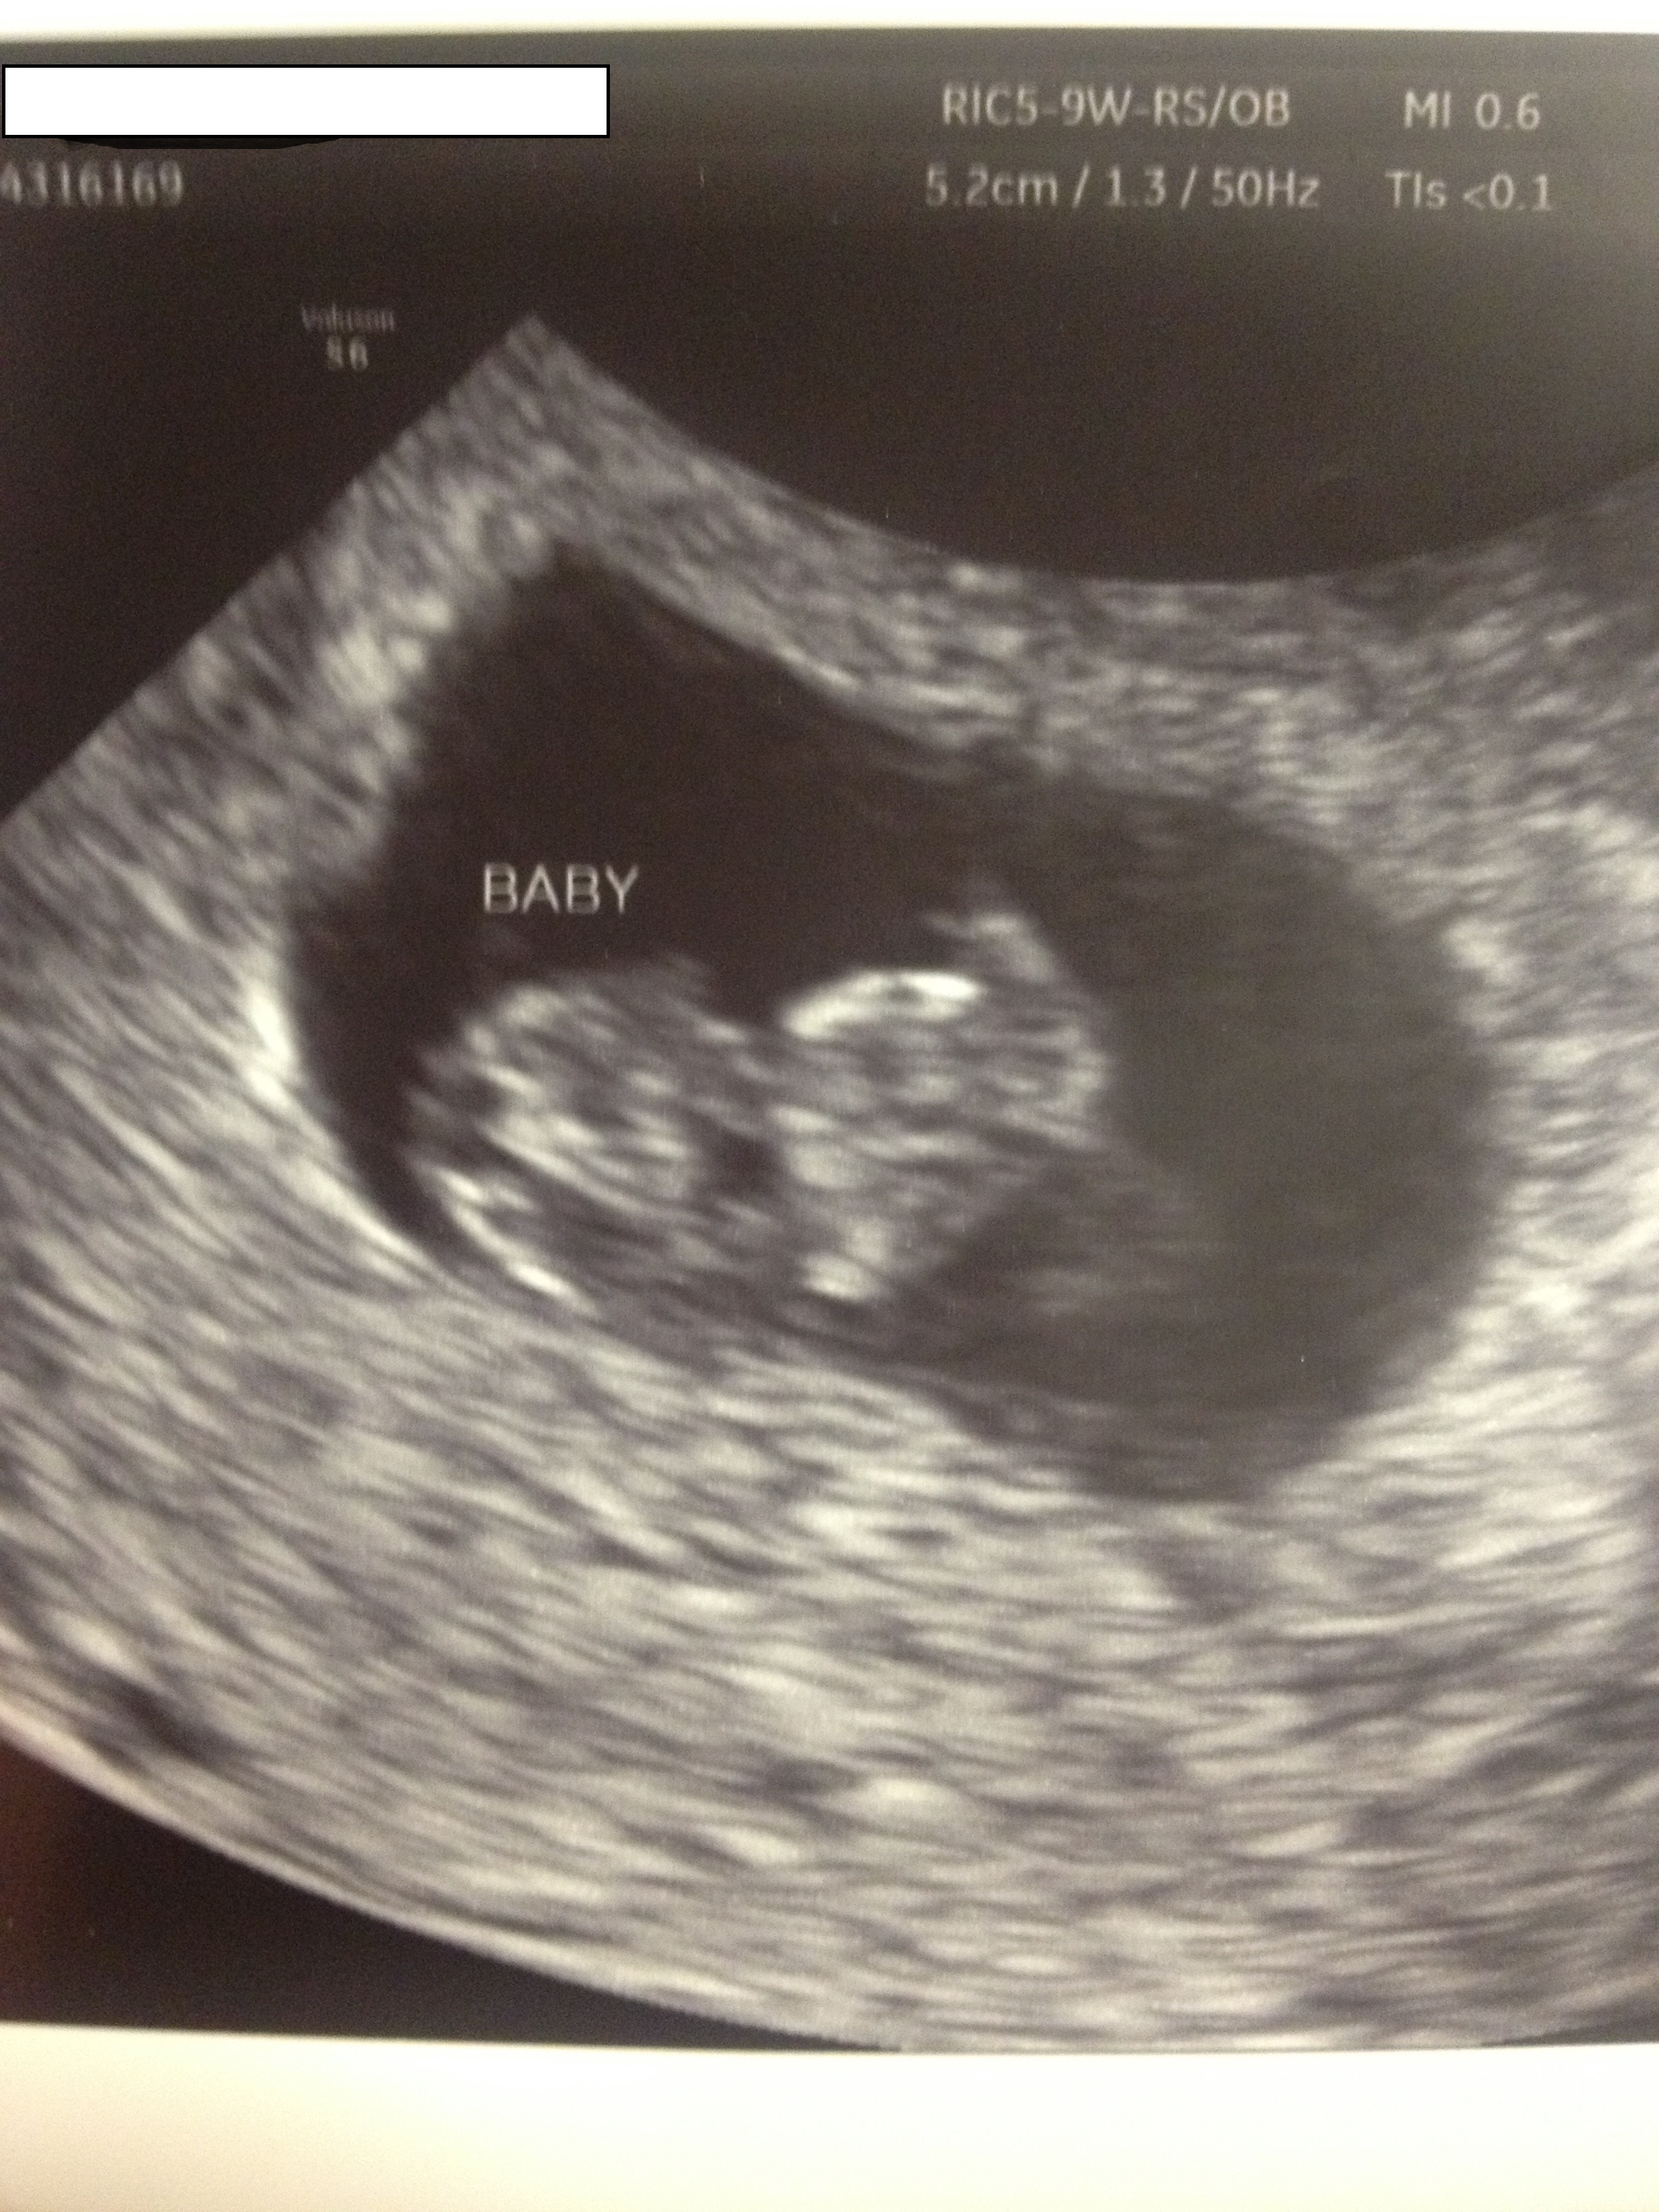

I graduated from my RE on Monday. I was 8w2d but I measured at 8w5d. I made my first OB appointment for May 19 and from what I gather it's an information session. I'm looking forward to it and hoping that I'll get another ultrasound but I don't think that I'll be that lucky.

Here's the picture from Monday .... My Little Bean.